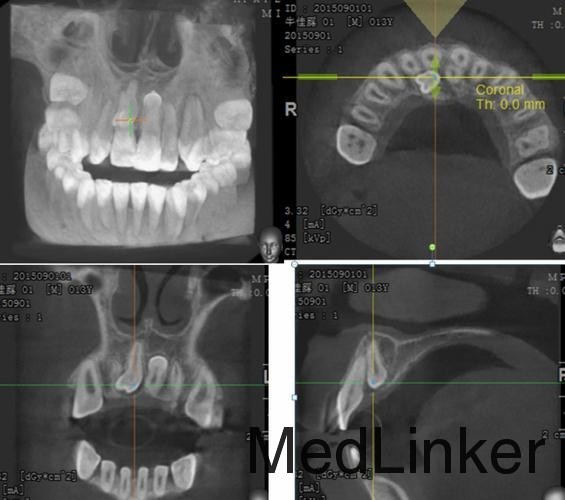

患者,男,拍牙片偶然发现前牙多生牙要求拔除,平素体质一般,无药物、食物过敏史,无高血压、心脏病等系统病史。

曲面断层片和牙科CT检查